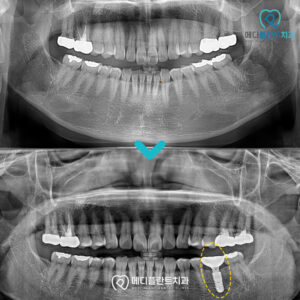

춘천수면임플란트 의식하진정으로 편안하게! 안녕하세요:) 춘천수면임플란트치과 메디플란트치과입니다. 유치가 빠지고 새롭게 자라나는 영구치는 말 그대로 평생 사용해야 하는 치아이기 때문에 한 번 상실하면 다시 자연적으로 회복되기 어렵습니다. 따라서…